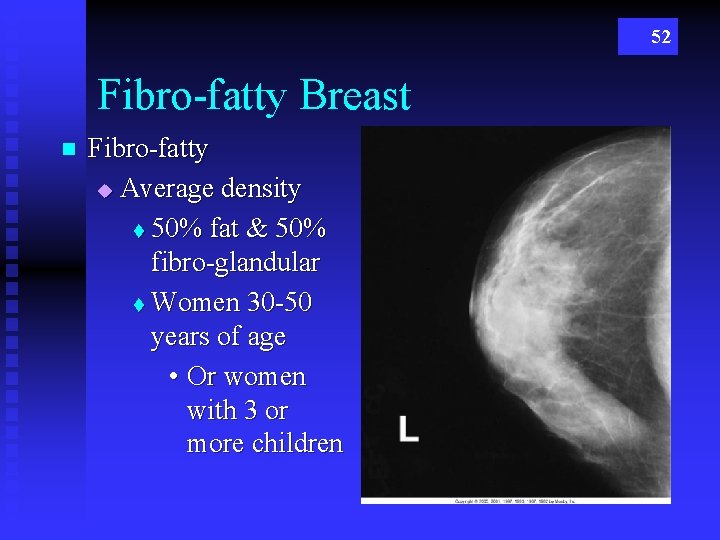

52 Fibro-fatty Breast n Fibro-fatty u Average density t 50% fat & 50% fibro-glandular t Women 30 -50 years of age • Or women with 3 or more children